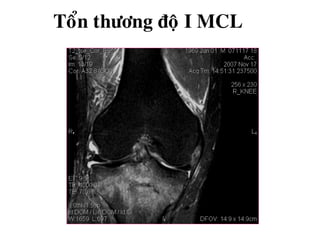

TOÅN THÖÔNG DAÂY CHAÈNG BEÂN

Ñoä 1: Taêng tín hieäu/ T2W ôû moâ phía trong daây chaèng

(giaõn daây chaèng möùc ñoä nheï).

Toån thöông ñoä I MCL